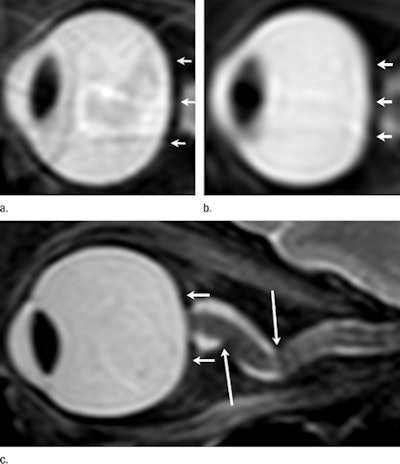

| Sagittal oblique T2-weighted MR images show a left eye (a) before long-term exposure to microgravity. Convexity of posterior globe is noted (arrows). Another left eye image (b) shows long-term exposure to microgravity, with the loss of convexity of the posterior scleral margin (arrows). The right eye (c) of a different astronaut notes two abruptly angulated foci (long arrows) in optic nerve sheath and posterior globe flattening (short arrows). Images courtesy of Radiology. |

Nine (33%) of the 27 astronauts with more than 30 days of cumulative lifetime exposure to microgravity experienced more cerebral spinal fluid space surrounding their optic nerve, while six astronauts (22%) with more than 30 days in space exhibited flattening of the rear of their eyeball. Four astronauts (15%) in the same group showed bulging of the optic nerve, while three astronauts (11%) displayed changes in the pituitary gland and its connection to the brain.

The same types of abnormalities are seen in cases of intracranial hypertension where no cause can be found for increased pressure around the brain. The pressure causes swelling between the optic nerve and the eyeball and eventually can result in impaired vision.